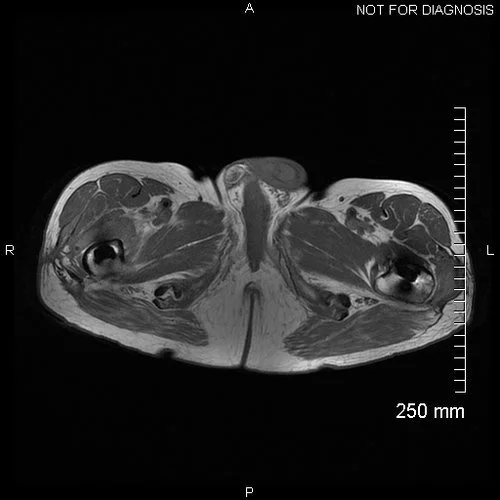

We requested an MRI pelvis to assess soft tissue changes (see below).

Axial MRI showing significant fluid collections around both hips, with considerable abductor muscle destruction. The fluid collection around the right hip extends to the wound.